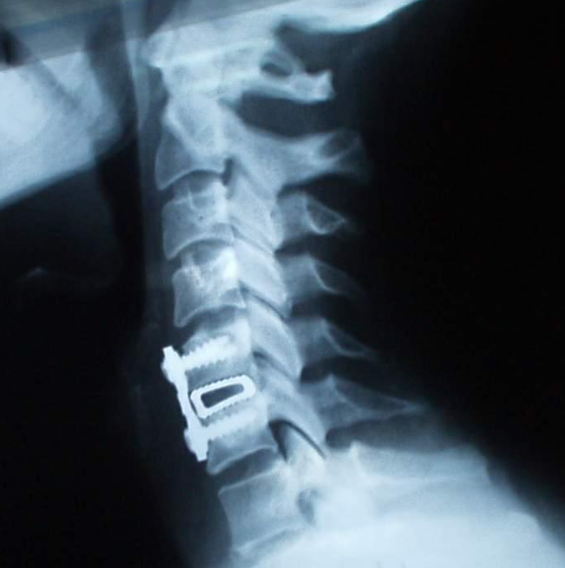

약물치료, 물리치료 및 주사치료가 효과가 없을 경우, 수술적 치료를 진행해야 합니다. 수술적 치료에는 대표적으로 내시경 신경감압술, 인공디스크삽입술 등이 있습니다.

인공디스크 삽입술은 탈출한 디스크를 제거하고, 특수제작된 인공디스크를 삽입하는 방법의 수술로, 수술 이후 척추의 퇴행성 변화를 최소화활 수 있는 수술 방법입니다.